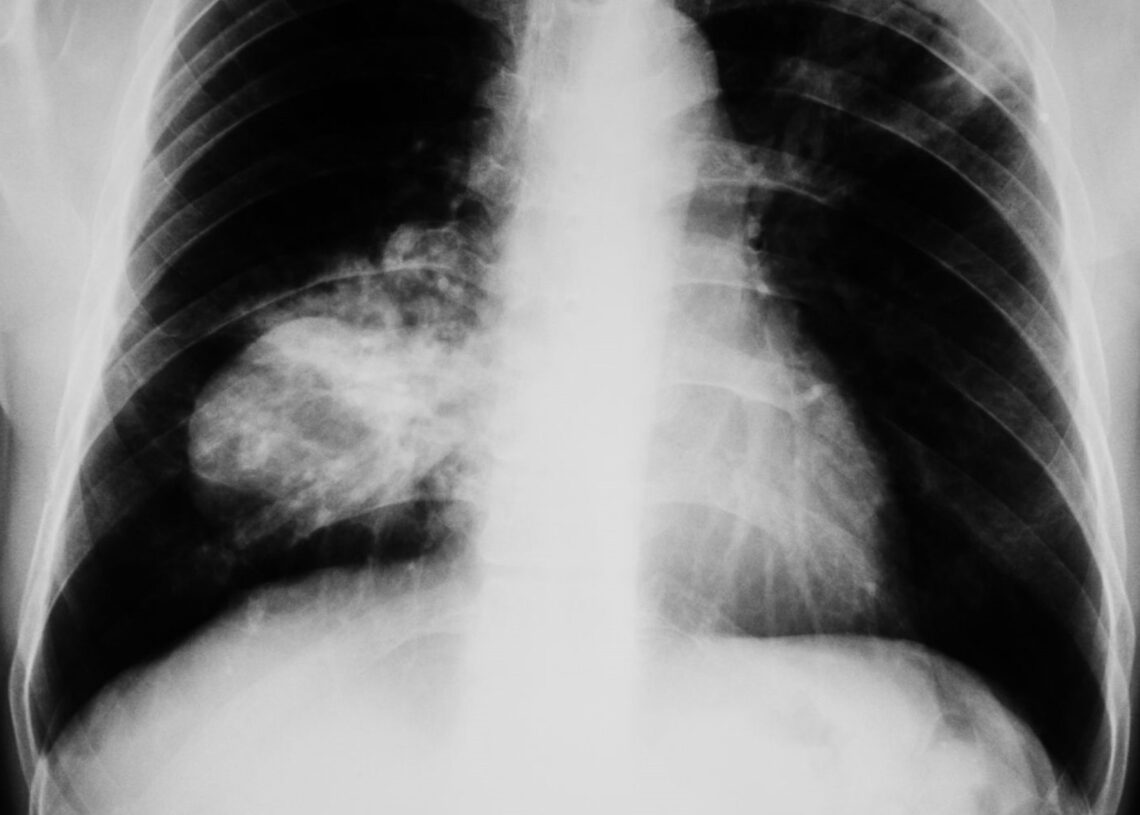

La doctora Dolores Isla, presidenta de ICAPEM y jefa de Oncología Médica en el Hospital Lozano Blesa, ha destacado la necesidad de mejorar la detección temprana del cáncer de pulmón en mujeres. Este llamamiento se realizó durante un evento coorganizado por ICAPEM y la Asociación Española de Afectados por Cáncer de Pulmón (AEACaP), con apoyo de la Fundación PharmaMar.

“El cáncer de pulmón de célula pequeña sigue siendo uno de los grandes retos clínicos. En el caso de las mujeres, su abordaje requiere un análisis más profundo, ya que pueden existir diferencias en sus factores de riesgo, características clínicas, evolución y respuesta a los tratamientos”, apuntó la doctora Isla.

El cáncer de pulmón de célula pequeña en mujeres, que representa el 15% de los diagnósticos de este tipo de cáncer, es especialmente agresivo y ha visto un incremento en su incidencia entre mujeres recientemente. Durante el evento, se aprobó un Manifiesto que destaca los principales desafíos para las mujeres con este diagnóstico y sugiere acciones específicas para mejorar su cuidado.